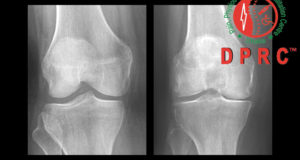

“অষ্টিওআথ্রাইটিস অব নি” এবং চিকিৎসা।

অষ্টিওআথ্রাইটিস অব নি কি? “অষ্টিওআথ্রাইটিস অব নি” বা হাটু ব্যথা, শুধু ক্ষয় জনিত রোগেই নয় এর কারন বিভিন্ন। তবে সবচেয়ে বেশি ...

অস্টিওআর্থ্রাইটিস হওয়ার কারণ: ক) বয়সের কারণে বয়স বাড়ার সাথে সাথে ক্রমাগত ব্যবহারে কার্টিলেজের ধীরে ধীরে ক্ষয় হতে থাকে এবং এই ...